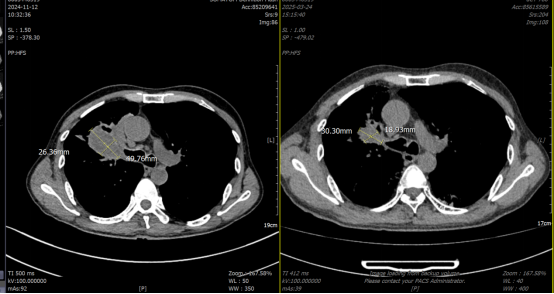

疗效评估:2025-3-24 放疗结束后1个月,行胸部CT平扫,对比放疗前(2024-11-12):右肺上叶恶性肿瘤伴纵隔、右肺门淋巴结转移治疗后复查,较前肿块及淋巴结、上叶阻塞性肺炎范围有所缩小。